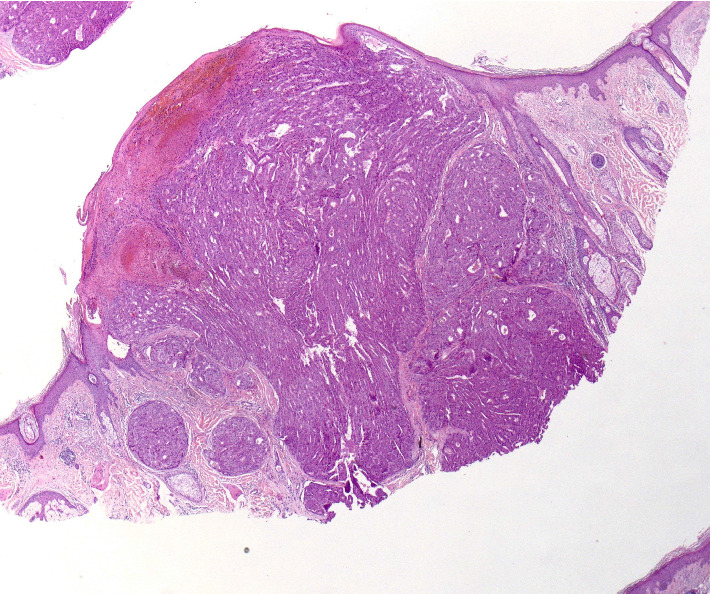

Introduction: Cutaneous metastases of hepatocellular carcinoma (HCC) are uncommon but important to recognize for timely diagnosis and management. Case Presentation(s): We present a case of a 70-year-old man with a history of HCC who developed a painless nodule on the scalp. Histopathological examination and immunohistochemistry confirmed the nodule as cutaneous metastasis of HCC. The patient had previously undergone transarterial chemoembolization and surgery for HCC, with no evidence of disease for a period before presenting with the cutaneous lesion. Conclusion: Cutaneous metastasis of HCC is rare but signifies advanced disease. This case underscores the importance of considering cutaneous manifestations in patients with a history of HCC and highlights the need for routine follow-up and early intervention to improve patient outcomes.